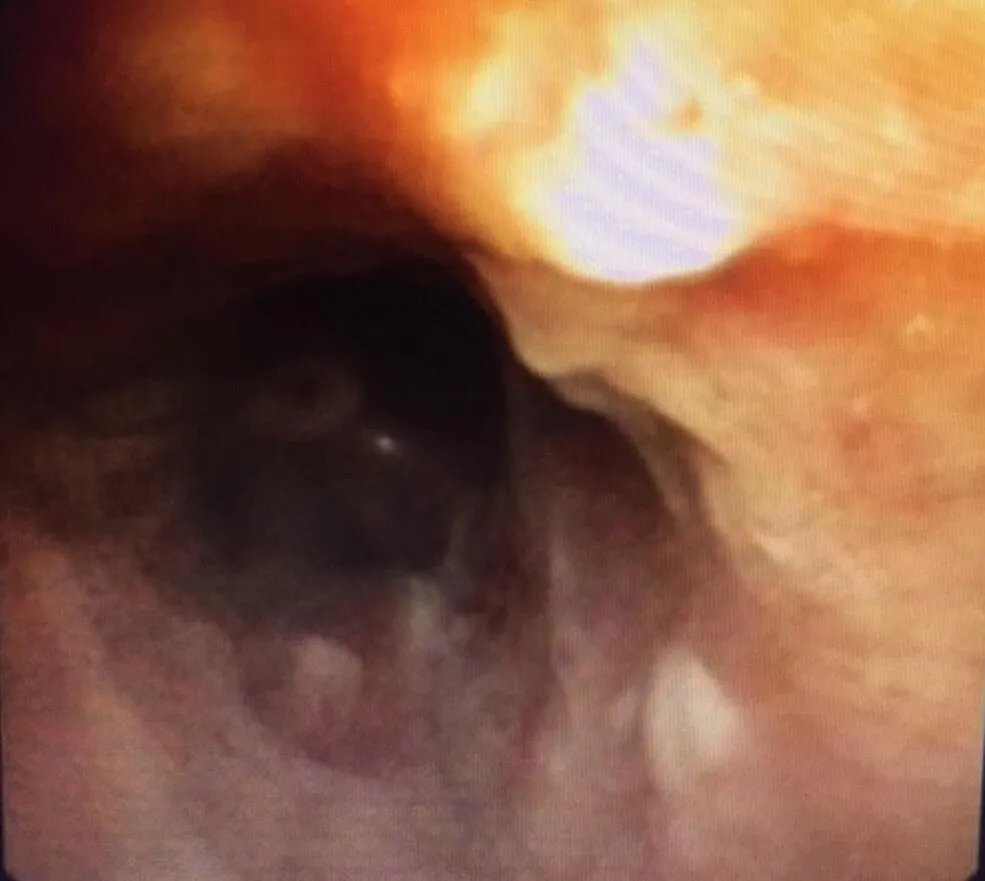

Người bệnh được nhập viện vào lúc 11 giờ 45 ngày 23-9 trong tình trạng ho nhiều, khó thở. Các bác sĩ của bệnh viện đã khẩn trương tiến hành hội chẩn và quyết định nội soi phế quản cấp cứu để gắp dị vật khí quản, giải phóng tắc nghẽn đường thở, nhằm cứu sống người bệnh.

Dị vật là 1 cầu răng sứ 4 răng hàm dài 3,5cm đã bị rơi vào khí phế quản trong quá trình lắp răng giả cho người bệnh.

Đây là một kỹ thuật y khoa khó vì dị vật quá to và trơn nhẵn do răng giả làm bằng sứ. Tuy nhiên với những trang thiết bị hiện có, Bệnh viện Phổi Trung ương có thể loại bỏ hoàn toàn các loại dị vật đường thở.